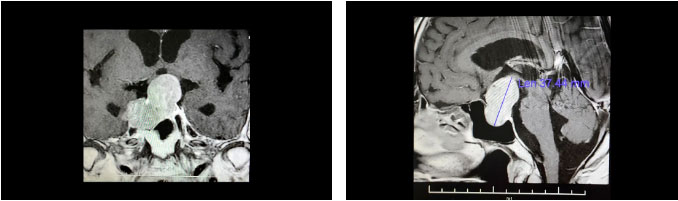

鞍區(qū)MRI平掃+增強(qiáng)顯示,蝶鞍顯著擴(kuò)大,鞍底下陷,見一團(tuán)塊狀異常信號灶,超蝶鞍生長,鞍膈處見“腰征”,瘤體輪廓尚清;腫塊矢橫高徑約 3.7 × 4.5 × 3.7cm。病變向鞍上生長,占據(jù)鞍上池,推移視交叉上抬、分界模糊;向下生長,破壞鞍底,嵌入蝶竇內(nèi);向鞍旁生長,侵及兩側(cè)海綿竇,右側(cè)海綿竇包裹1/2、分界欠清。

▲ 影像顯示垂體占位,侵犯蝶竇及海綿竇